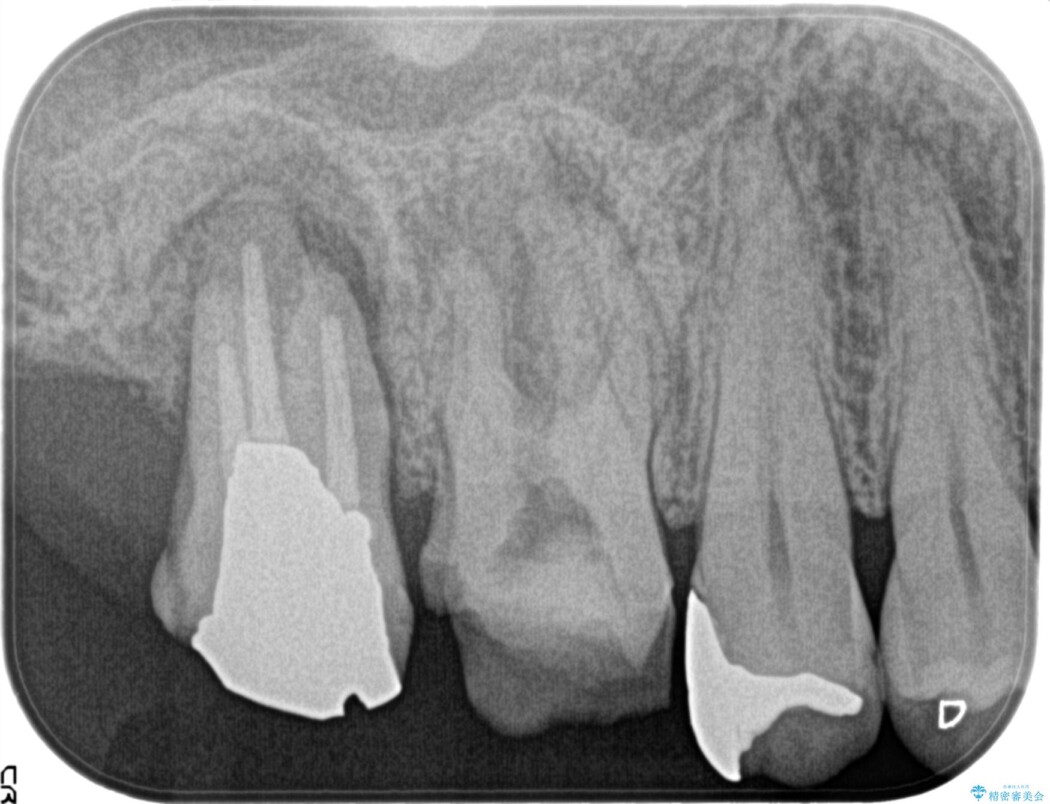

検査をしたところ不可逆性歯髄炎と認めました。

虫歯を取り除いてみると深いクラックラインが明確に確認できたため、全て除去して抜髄処置を行う方針としました。